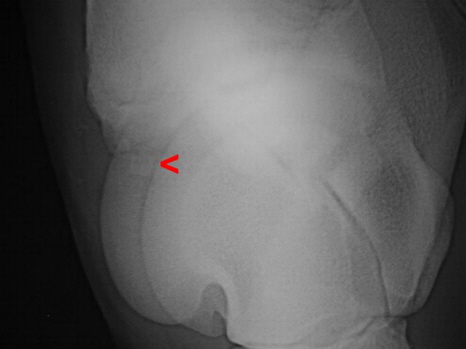

Chip Sprunggelenk